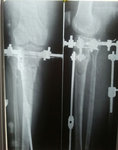

Дата операции 18.06.2015г.

Дата снятия аппаратов 20.02.2016г.

Срок лечения 8 месяцев.

Причина длительного сращения - Гормональный сбой у женщин после 40 лет – очень частая проблема.

Какие возрастные изменения происходят в организме у женщин с возрастом после 40 лет?

Слабеют мышцы, хуже работают легкие, уменьшается их объем, уменьшается потихоньку и костная масса, что ведет к меньшей гибкости и большей хрупкости костей, остеопорозу, длительному сращению переломов. Другое дело, что одни и те же изменения в организме у одной женщины заметны уже после 40 лет, у другой - в семьдесят, а у третьей - и к девяноста лишь слегка.

Все эти изменения, зависят от уровня женских половых гормонов, которые после 35 лет снижаются.

Помните, что гормональный фон индивидуален у каждой женщины, и только опытный врач сможет помочь вам подобрать подходящие контрацептивы и лечебные препараты.

По этому, нашей пациентки было рекомендовано консультация, обследование и параллельное лечение у гинеколога - эндокринолога.